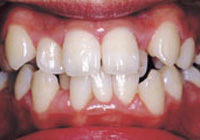

症例4:上顎前突(出っ歯)

治療前

治療後